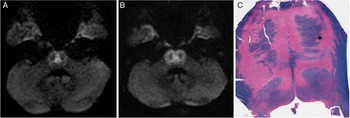

A 54-year-old man with decompensated alcoholic cirrhosis was admitted to the hospital with hepatic encephalopathy. Rifaximin, lactulose, albumin infusions, and tube feeds were initiated. Three days after admission, his hemoglobin dropped due to presumed gastrointestinal bleeding, for which he received blood transfusion and bolus normal saline. Electroencephalography 12 days after admission for decreased level of consciousness revealed nonconvulsive status epilepticus, while brain magnetic resonance imaging (MRI) 13 days after admission showed central pontine diffusion restricting signal abnormality resembling a trident (Figure 1A). He was intubated for airway protection and seizure control. Electrographic seizure activity ceased with levetiracetam, clobazam, and propofol. Upon weaning of propofol, seizures did not recur but his level of consciousness was persistently decreased. On examination, his Glasgow Coma Scale was 3T. He was unarousable. Pupils were small and minimally reactive. Corneal reflexes were present. Horizontal eye movements were limited. Gag reflex was not elicitable. His legs were hypertonic and hyperreflexic. There was no withdrawal from painful stimuli. Repeat MRI 19 days after admission showed ventrolateral progression of pontine diffusion restricting signal abnormality with sparing of the corticospinal tracts, resembling a pig’s snout (Figure 1B). Additional signal abnormality of the thalamus, basal ganglia, and frontoparietal cortices was also observed. On chart review, we noted that over the first 6 days of his admission his serum sodium increased from 132 to 161 mmol/L (normal: 135−145 mmol/L), with a maximum 24-h increase of 8 mmol/L. The significant rise in his serum sodium coupled with his radiographic findings was concerning for osmotic demyelination syndrome (ODS). His serum sodium was closely monitored thereafter to avoid further fluctuations. No clinical improvement occurred, and after discussion with his family, comfort care measures were implemented. He passed away 1 month after admission. Autopsy was performed, and Luxol fast blue stain confirmed extensive pontine demyelination that relatively spared the peripheral pons and corticospinal tracts (Figure 1C). Findings compatible with extra-pontine demyelination and acquired hepatocerebral degeneration were also observed.

Figure 1: Neuroimaging and pathological depiction of the “pig’s snout” sign in osmotic demyelination syndrome. On serial brain MRI, axial diffusion-weighted imaging (DWI) on day 13 of admission (A) shows central pontine hyperintensity (“trident” sign) that evolved to more extensive pontine hyperintensity (“pig’s snout” sign) on day 19 of admission (B). Corresponding apparent diffusion coefficient map confirmed true diffusion restriction (not shown). On autopsy, Luxol fast blue stain confirmed extensive pontine demyelination that relatively spared the corticospinal tracts (C) as the cause of the pig’s snout appearance.

ODS is typically a complication of treatment of patients with severe hyponatremia. Reference Martin1 However, additional risk factors (e.g., alcoholism, malnutrition, liver disease) may predispose to ODS even with milder degrees of hyponatremia, as in our patient. Reference Martin1 While initially described as a disease of the pons (central pontine myelinolysis), later recognition of lesions outside the pons (extra-pontine myelinolysis) render the broader term ODS more appropriate. Reference Martin1 The precise underlying disease mechanisms are unclear, but demyelination is thought to be due to osmotic stresses causing oligodendrocyte death. Reference Ruzek, Campeau and Miller2 The "trident" sign is a classical neuroimaging finding in ODS that reflects demyelination of crossing pontocerebellar fibers. Reference Ruzek, Campeau and Miller2 In contrast, the “pig’s snout” sign or “piglet” sign has only been rarely reported and refers to larger pontine lesions that extend ventrolaterally while sparing the peripheral pons and corticospinal tracts. Reference Wagner, Mueller-Schunk and Schankin3,Reference Beh4 Progression from the trident sign to the pig’s snout sign in our case supports that they exist on a spectrum of disease severity. Pathological findings in our case confirm that the pig’s snout sign reflects extensive pontine demyelination, further supporting a severe form of ODS. Recognition of the pig’s snout sign can aid in the accurate diagnosis of ODS.